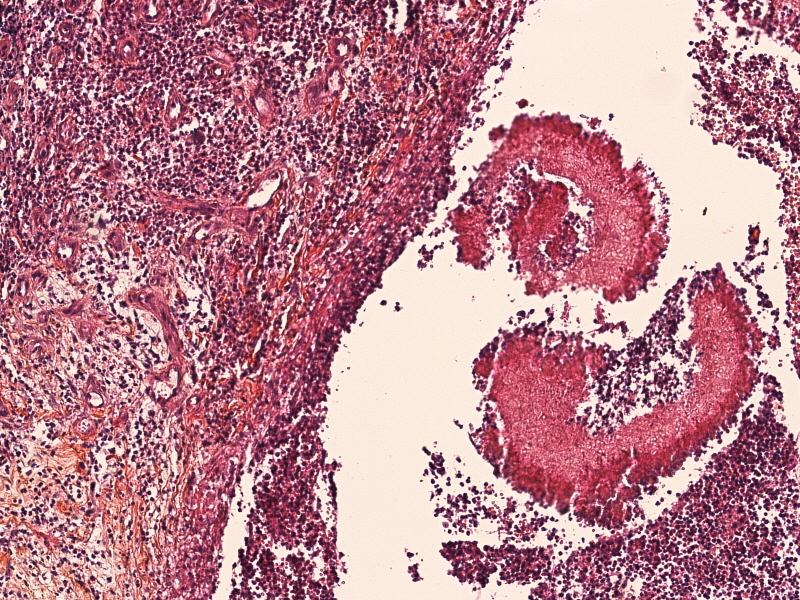

The second task involved classifying the detected grains into Actinomycetoma (bacterial) or Eumycetoma (fungal). Correct classification is critical for determining treatment, as bacterial infections are treated with antibiotics, while fungal infections often require antifungal therapy or surgical intervention. For each detected Mycetoma grain, the algorithm was supposed to give a classification label indicating whether the detected grain is Actinomycetoma or Eumycetoma. Fig.1 illustrates typical histopathological images of both classes and their segmentation masks.

Figure 1: Representative histopathological images of mycetoma. The first row shows examples of the two classes: Actinomycetoma (AM) and Eumycetoma (EM). The second row presents the corresponding segmentation masks highlighting the mycetoma grains within the tissue samples.